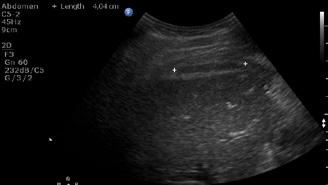

A opera sau a nu opera? Raspunsul ecografistului

Dr. Dan Adrian Stănescu 24